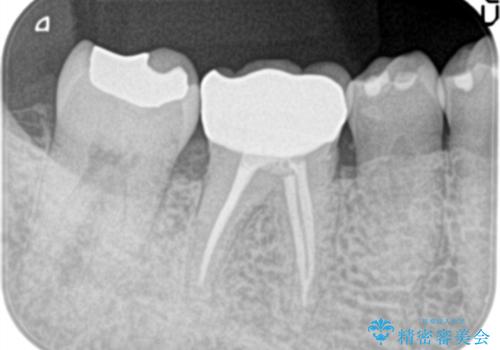

- 1週間前から冷たいもので強い持続痛を感じることを主訴に来院されました。

歯髄診断と痛みの再現により原因歯を特定し、症候性不可逆性歯髄炎の診断となりました。

根管治療〜オールセラミッククラウン(エクセレント)の治療を行なっております。

- 精密根管治療(イニシャルケース,大臼歯):122,000円、ファイバーコア:22,000円、仮歯:11,000円、オールセラミッククラウン(エクセレント):200,000円費用は治療当時の料金となります